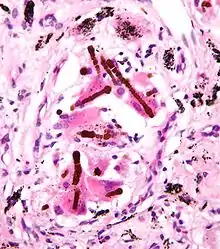

- Malignant mesothelioma: an aggressive and incurable tumour arising from mesothelial cells of the pleura (the lining of the thoracic cavity).

Mechanisms of carcinogenicity

Stanton and Layard hypothesized in 1977–78 that toxicity of fibrous materials is not initiated by chemical effects;[26] that is, any trigger-effects of asbestos must presumably be physical, such as mechanical damage which might disrupt normal cell activity—especially mitosis.

There is experimental evidence that very slim fibers (<60 nm, <0.06 μm in breadth) tangle destructively with chromosomes (being of comparable size).[27][28] This is likely to cause the sort of mitosis disruption expected in cancer.